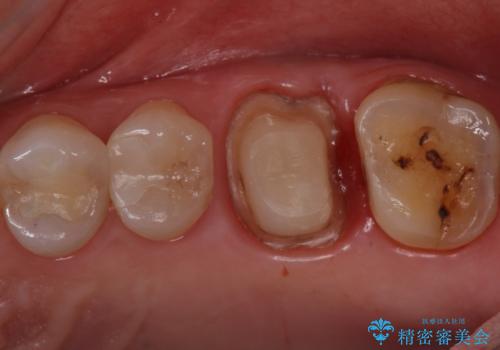

- 検査の結果被せ物の下に虫歯が確認された患者様です。

虫歯を取りきった後セラミッククラウンでの修復処置を行います。

被せ物の裏側の虫歯は被せ物を取らないと除去できません。

今回は過去に治療された部分をすべてやり直しました。